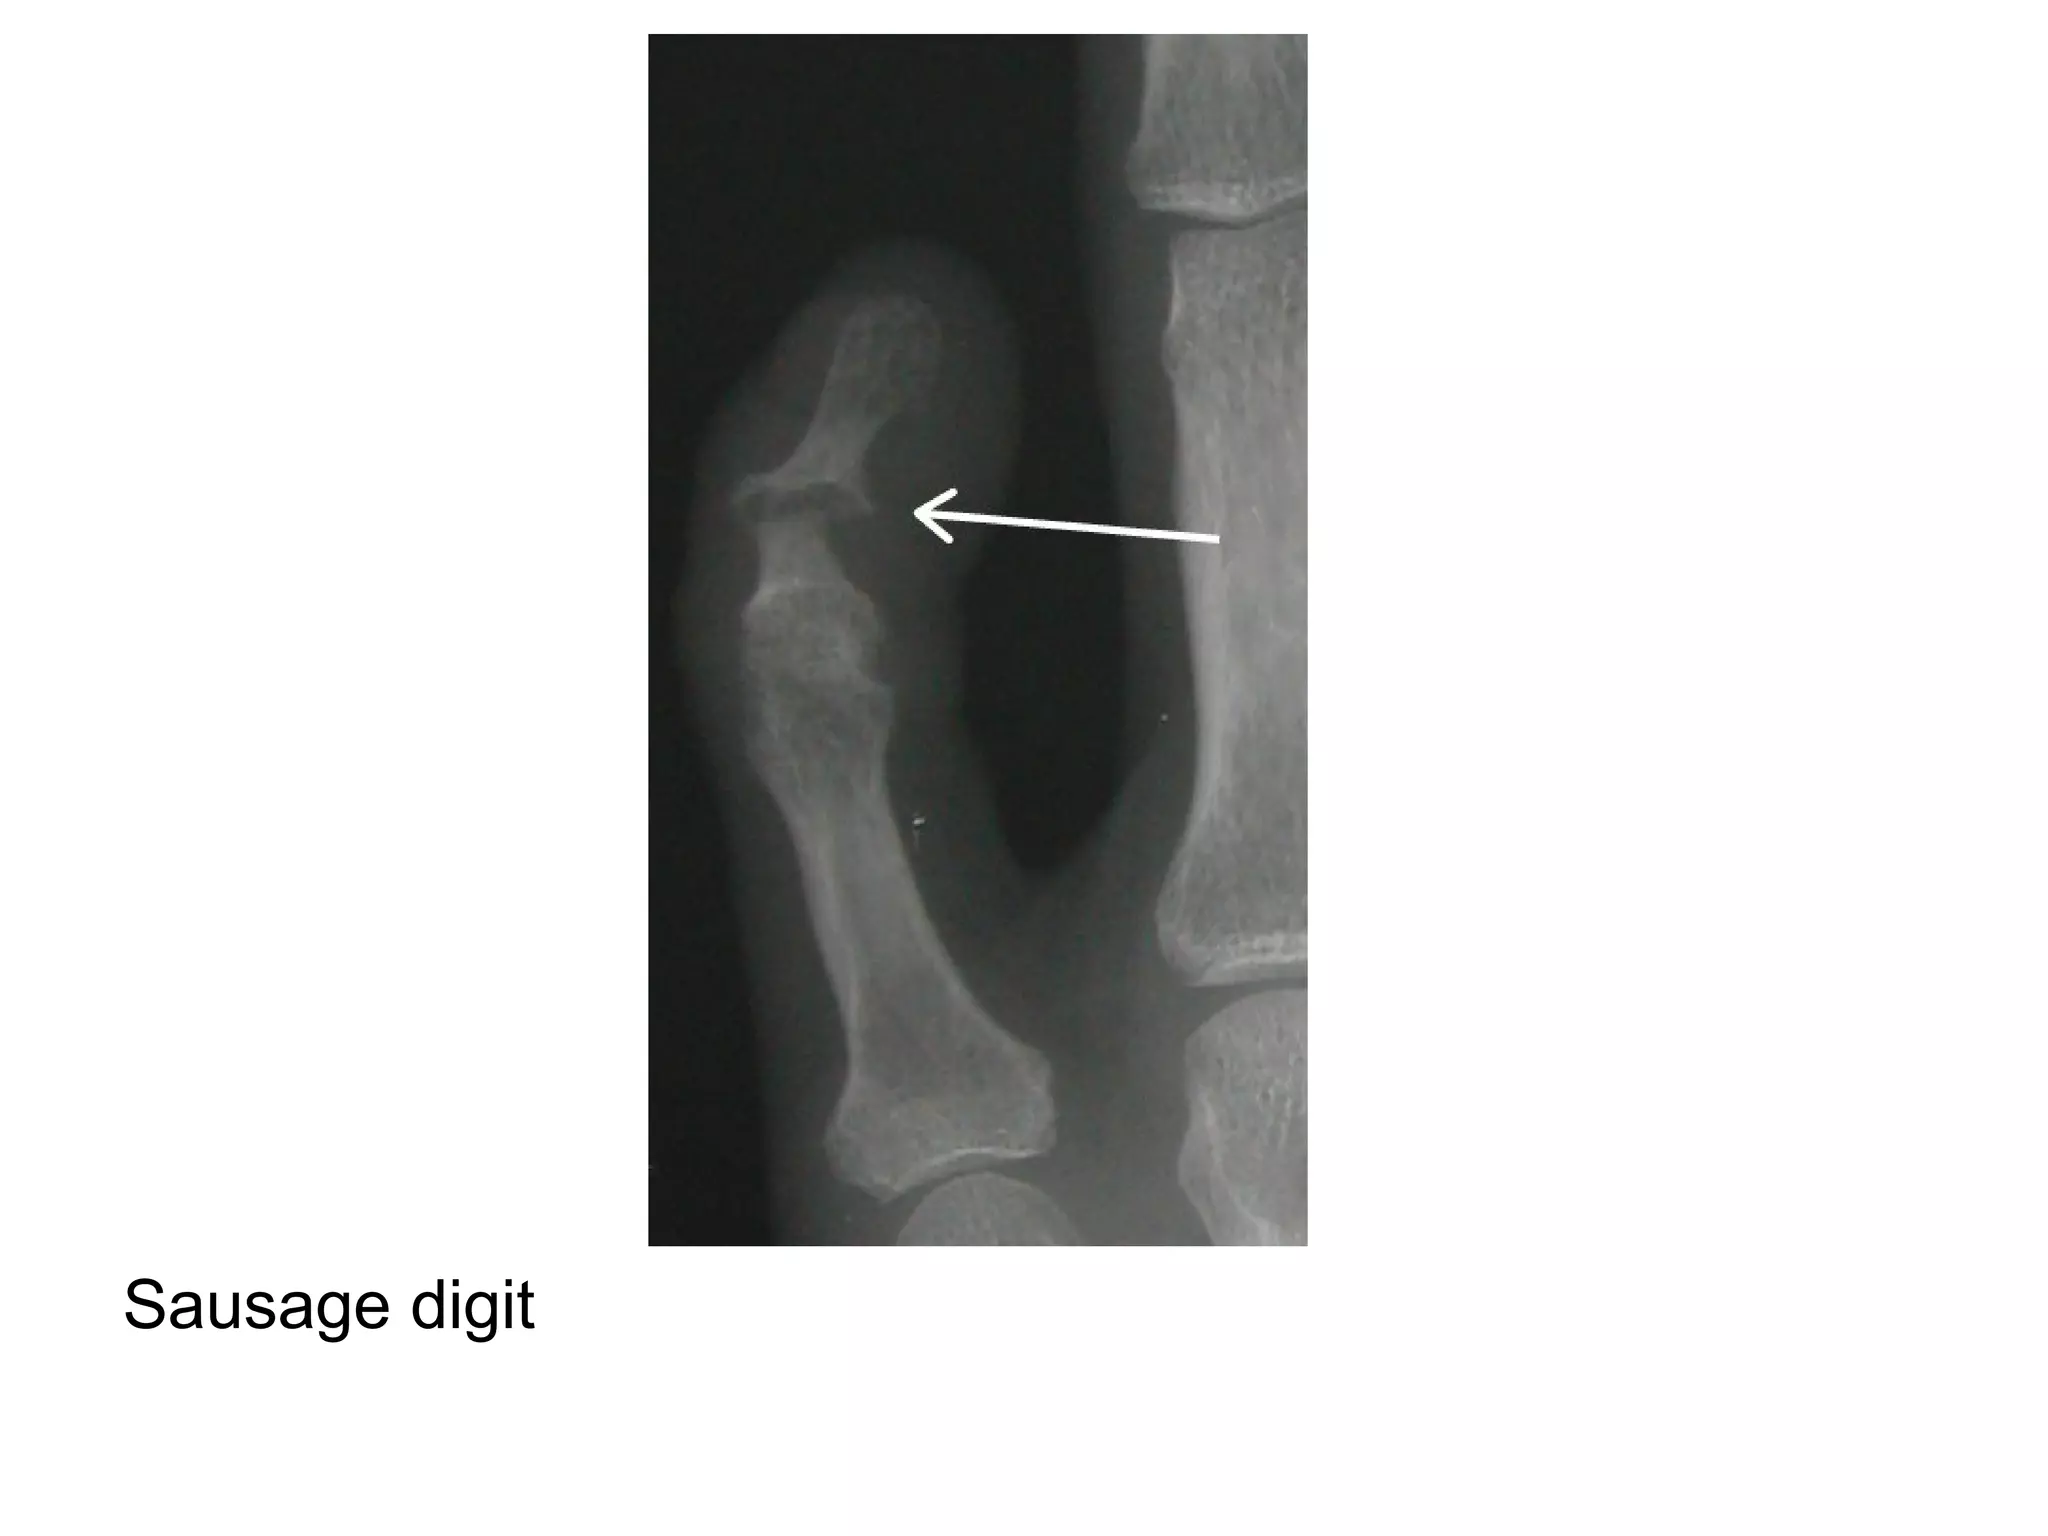

-sausage digit : soft tissue swelling of entire

digit

Sausage digit